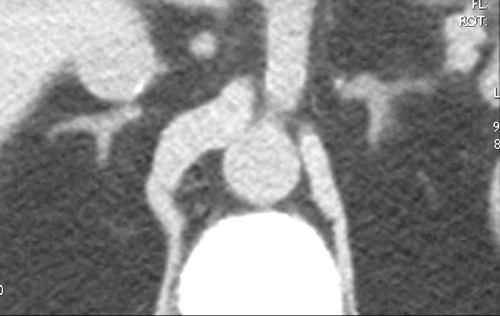

This series of three images reflects a study called “adrenal vein sampling” which requires the simultaneous catheterization of the adrenal veins. This procedure is used to identify relative and absolute concentrations of hormone secretion from the glands to distinguish between normal, bilateral hyperplasia, and unilateral adenoma.

The first image shows the catheters in each of the adrenal veins. The second image is a venogram of the right adrenal vein, and the third a venogram of the left. The venogram is mainly performed to confirm that the catheter is in the correct position, because the veins, particularly the right, may be difficult to find and other small veins coming into the IVC may masquerade as adrenal veins. It is absolutely essential to be in the “right place at the right time” for this test. Courtesy of: Ashley Davidoff, M.D. |

This image is an overlay and an enlarged version of the first image above. It shows the right catheter entering the short right adrenal vein, exiting from above the right gland, and entering the IVC. The left adrenal vein, which is longer, exits from below the left gland and enters into the left renal vein. The insert of the “duel” is a reminder of the short vein on the right and the long vein on the left. Courtesy of: Ashley Davidoff, M.D. |